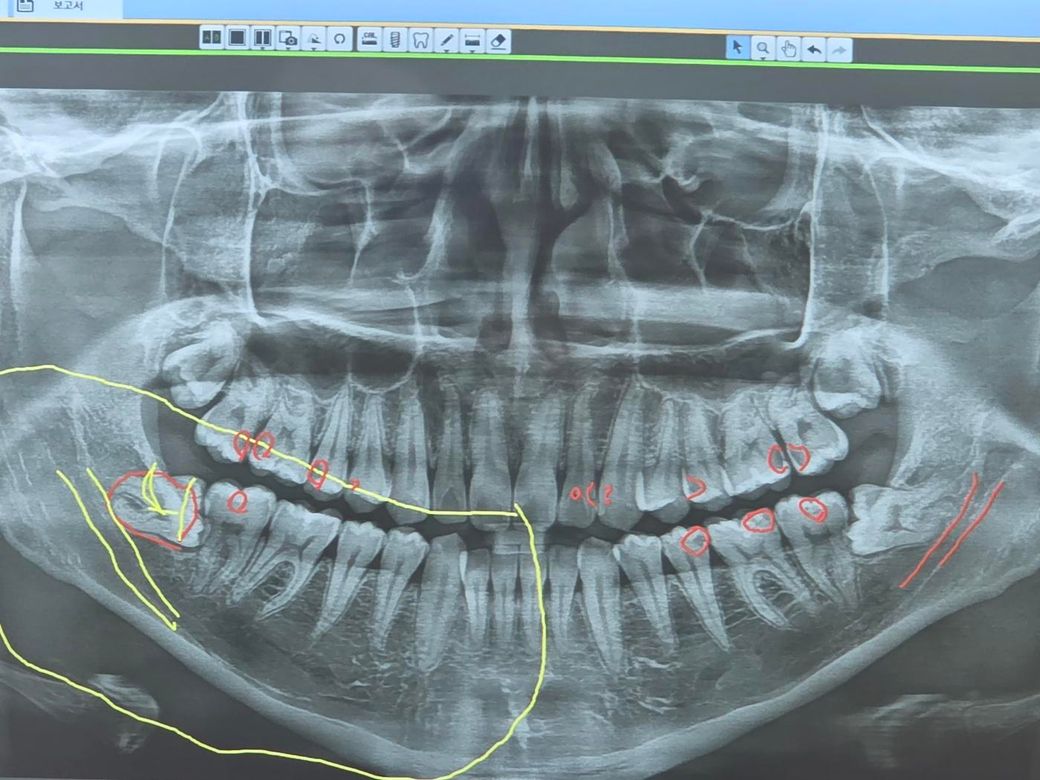

선생님들 제 치아입니다 크라운7개 필요하다는대

3일전부터 사랑니쪽 잇몸이 부어서 오을 발치할려고 갓었습니다. 잇몸 x레이를 찍고 충치가 너무 많다고 하십니다(충치 많은 건 알고있었습니다) 크라운은 7개 정도 해야되단고 말씀 하셨는대 선생님들 고견 부탁드립니다

사진으로 봤을 경우 충치가 여러 군데 있는것으로 보입니다.

인접면 충치의 경우에는 보철치료가 필요합니다. 큰 충치의 경우에는 크라운 그렇지 않다면 인레이 보철물을 이용해서 부분적으로 충치를 치료 할수 있습니다.

신경치료가 필요하지 않으며 인접면에 충치가 없다면 레진과 같은 재료로 간단하게 치료할수 있습니다.

엑스레이상 표시된 부분은 다 충치가 맞는것으로 보입니다. 깊은 충치는 신경치료하고 크라운 씌워주어야 합니다.